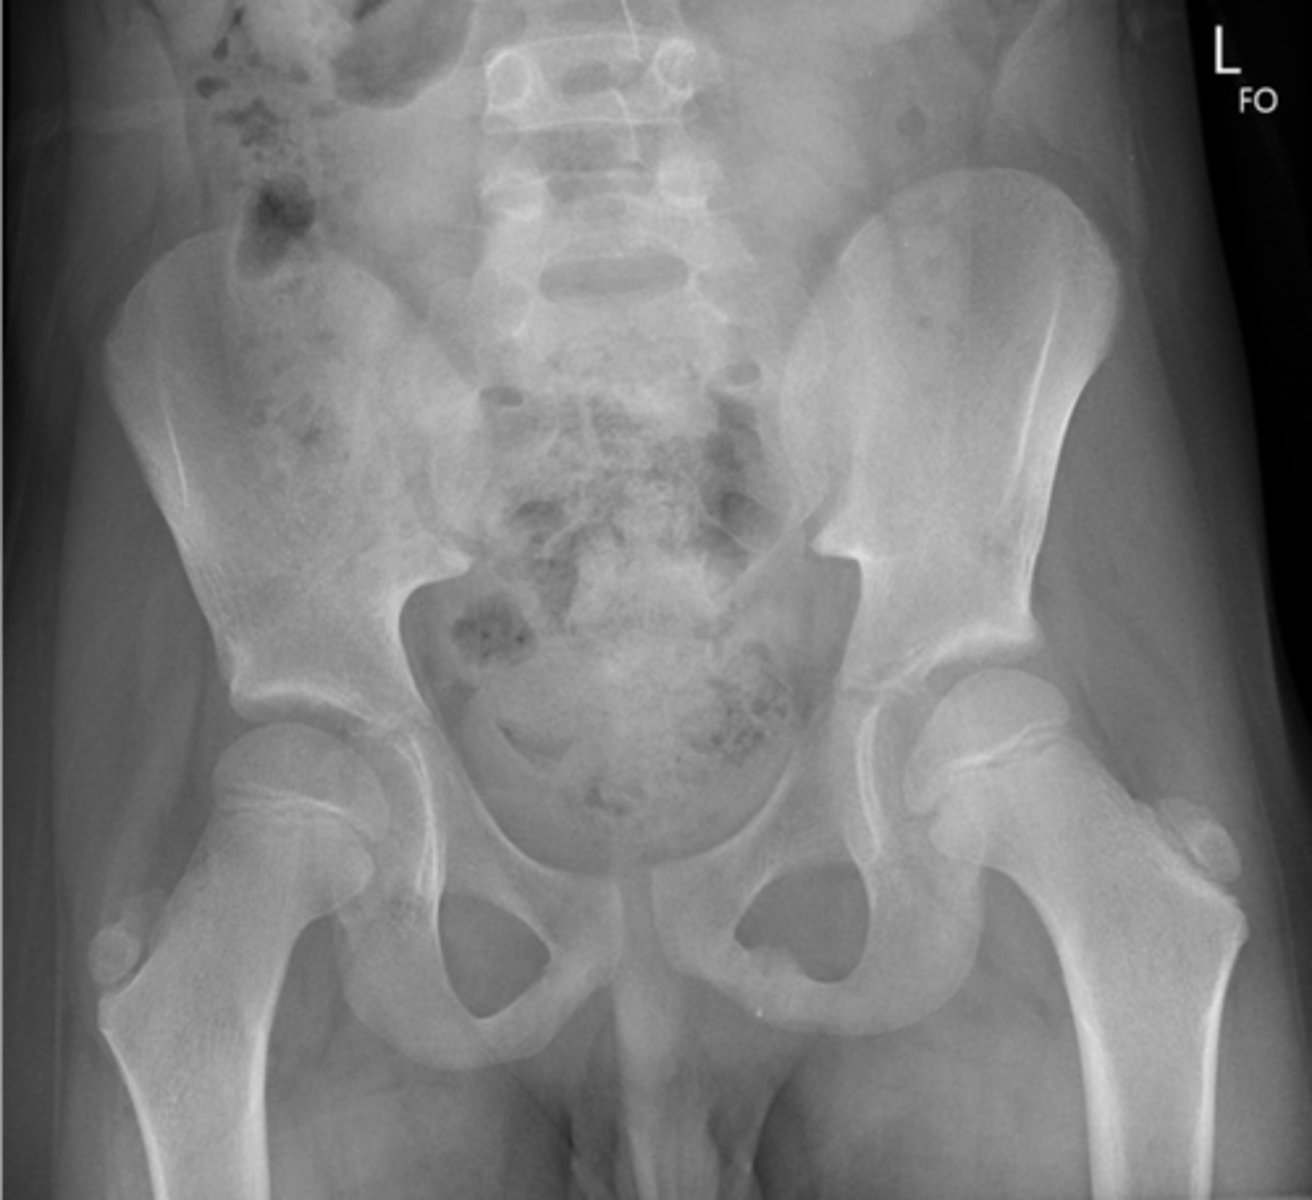

- AP pelvis

- Frog-leg pelvis

State the standard bilateral pelvis projections

2

New cards

AP pelvis

ID standard bilateral pelvis projection

<p>ID standard bilateral pelvis projection</p>

3

Frog-leg pelvis